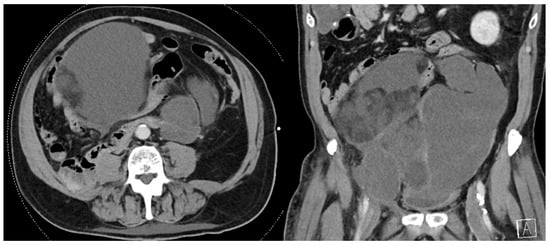

2. Imaging

- High-quality, contrast-enhanced CT imaging of the chest, abdomen, and pelvis should be performed when tumor recurrence is first identified.

- MRI may be useful to help delineate pelvic disease or extent of tumor involvement.